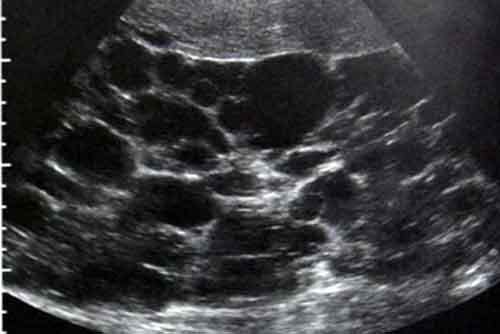

ADPKD - [Autosomal Dominant Polycystic Kidney Dz]

Describe the Disease - 7

ADPKD

Aneurysm (Berry)

Doomed [HTN and MVP]

[PrOteinuria AND Hematuria]

Kidney Failure (Early vs. Late onset) - Hepatomegaly occurs if cystic involvement

Differentation problem = Etx

Image: Renal Ultrasound which = Dx